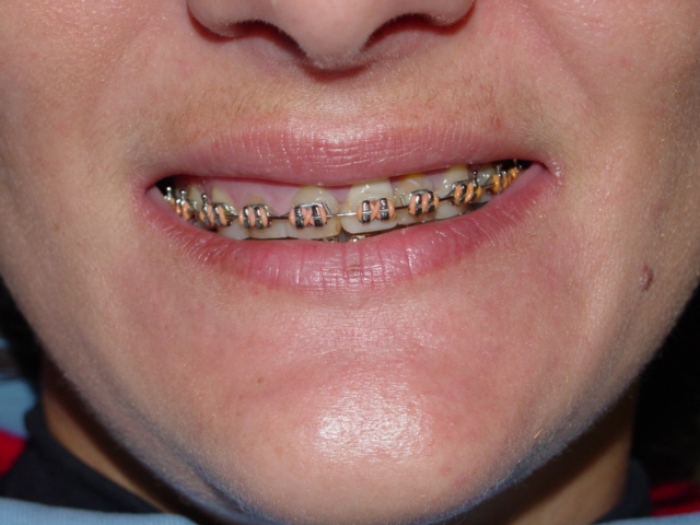

Sorriso final do caso terminado em Dezembro de 2011